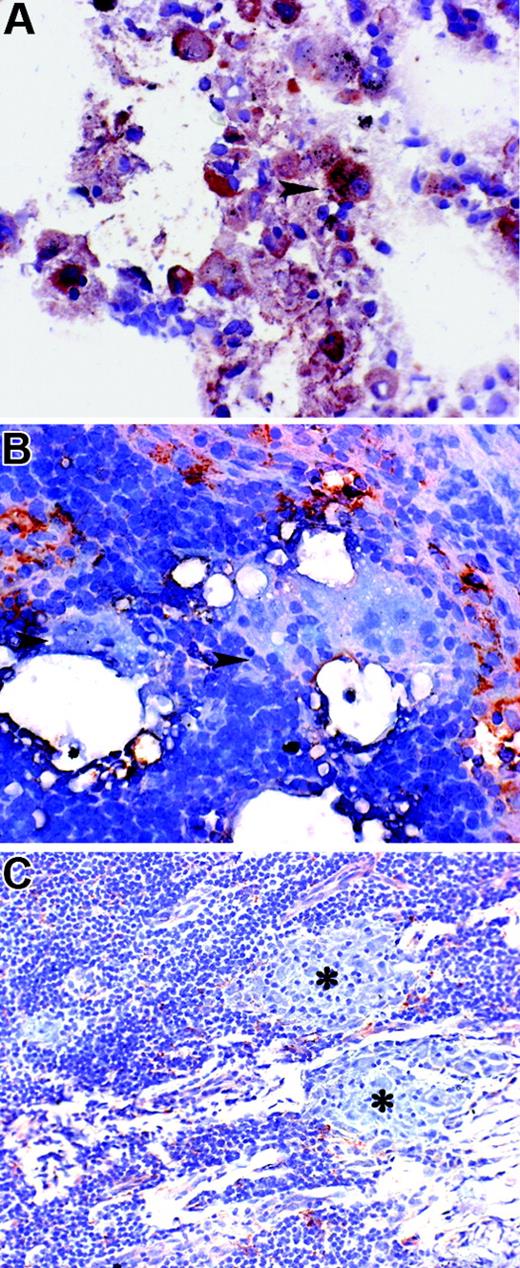

PTPγ expression correlates with a tolerogenic phenotype

We recently demonstrated that in patients with pancreatic cancer, DCs acquire a tolerogenic phenotype35 associated with a reduced capability to induce an allogeneic response and to release IFN-γ. We measured the level of PTPγ expression in moDCs derived from sex- and age-matched controls and from patients with advanced pancreatic cancer. The latter had diminished ability to induce T-cell proliferation (Figure 7A). Immature moDCs induced significantly higher IFN-γ production by T cells than did immature moDCs generated from patients (median, 1784 pg/mL; range, 1028-3425 pg/mL vs median, 1045 pg/mL; range, 521-1507 pg/mL; P = .006; Figure 7B). This feature is associated with an increased expression of PTPγ (P = .01; Figure 7C).

Tolerogenic phenotype of moDCs derived from patients with pancreatic cancer is associated with decreased PTPγ expression. (A) Allostimulatory function (MLR) of immature moDCs generated from patients with advanced or metastatic pancreatic carcinoma (n = 24, •) compared with control immature moDCs (n = 15, ○). Results are expressed as mean ± SD of [3H-TdR] uptake after 5 days of MLR culture in triplicate and show a reduced capability to stimulate T-cell proliferation by the former. CPM for T cells alone was 3963 ± 984. (B) IFN-γ production by allogeneic T cells stimulated by immature moDC from healthy donors (n = 15) and patients with advanced or metastatic pancreatic carcinoma (n = 15). Cytokine levels were detected by ELISA in cell-free supernatants collected from primary MLR before the addition of 3H-TdR. (C) PTPγ expression was increased in patients with metastatic pancreatic carcinoma (n = 9) compared with healthy donors (n = 11). (B-C) Median, 25th percentiles, 75th percentiles, minimum values, and maximum values are presented as vertical boxes and lines.